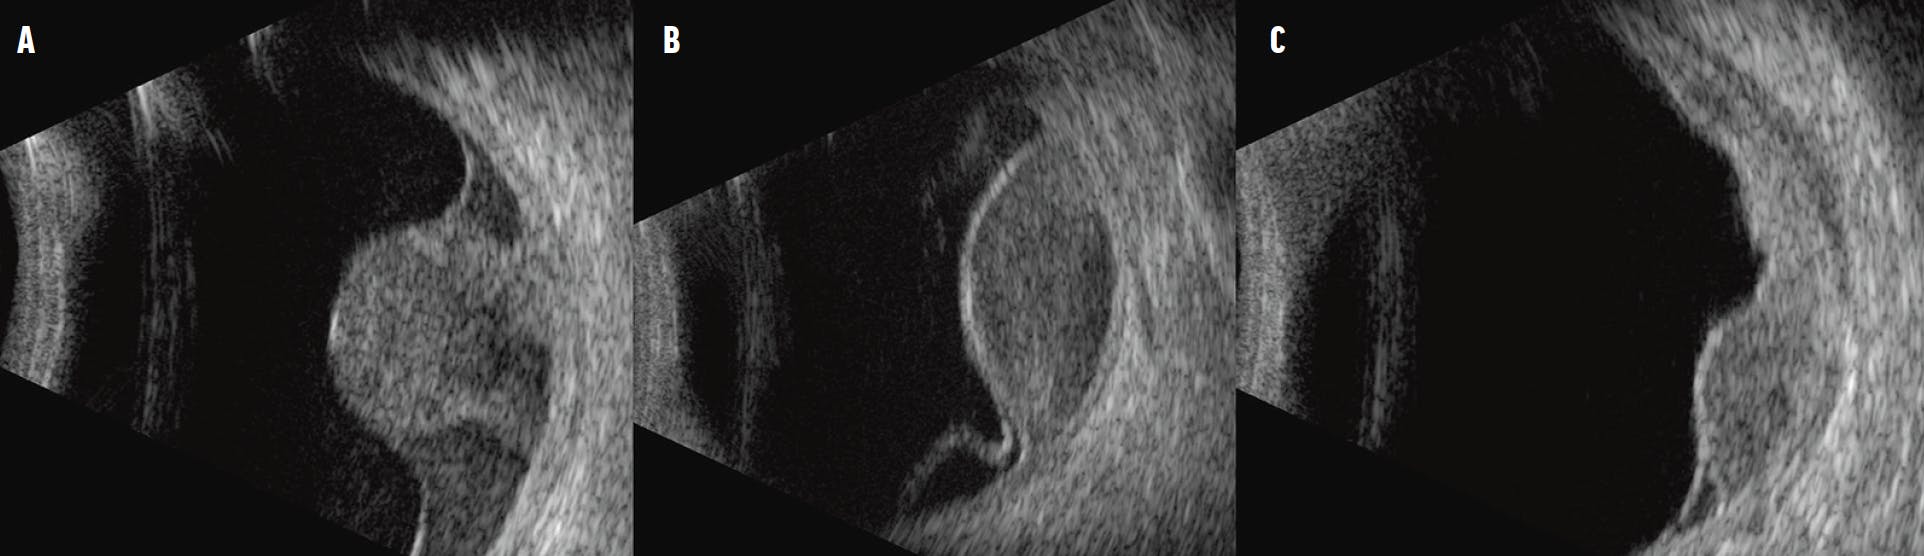

The diagnosis of uveal melanoma is primarily based on biomicroscopic examination and multimodal imaging, including ultrasonography.1 A typical finding during fundoscopy is a pigmented, dome-shaped nodular mass beneath the retinal pigment epithelium. However, some patients present with atypical clinical features or smaller lesions, for which ultrasonography can help confirm the diagnosis.2 B-scan ultrasonography can further reveal various tumor shapes, including the characteristic mushroom or collar-stud morphology, dome-shaped lesions, and, less frequently, multilobulated or minimally elevated tumors (Figure 1).3

<p>Figure 1. A mushroom-shaped tumor generally exhibits heterogeneous reflectivity characterized by acoustic hollowness at the tumor base and higher reflectivity toward the head (A). Note the distinguished homogeneous consistency of the dome-shaped choroidal lesion (B) and multilobulated melanoma (C).</p>

Figure 1. A mushroom-shaped tumor generally exhibits heterogeneous reflectivity characterized by acoustic hollowness at the tumor base and higher reflectivity toward the head (A). Note the distinguished homogeneous consistency of the dome-shaped choroidal lesion (B) and multilobulated melanoma (C).